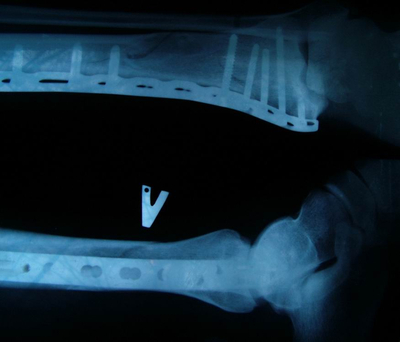

в январе 2021 на праздниках угораздило меня быть сбитым на пешеходном переходе. Очнулся в палате с гипсом на руке и ноге правой стороны. Не буду описывать процесс восстановления. Но то что автор описал я проходил дофига раз. Смысл в том что больничный открывается на 2 недели максимум, и если за это время ты не выздоровил то через комиссию продлеваешь ещё на 2 недели. Я сростался 3 месяца. Лифт в поликлинике работал раза 3 из всех моих посещений. Кто додумался травматолога сажать на 3й этаж? Каждое моё посещение это ад прыганья по ступенькам на 3й этаж. Потом ты прыгаешь на второй на комиссию, или на 4й на сдачу анализов. Или с 3го на первый в рентген а потом обратно на 3й показать снимки. Это был такой ад что аж страшно вспоминать.